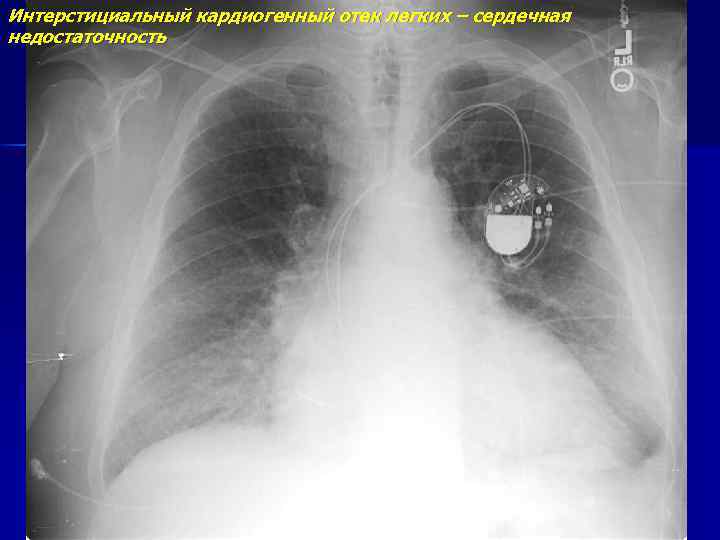

Интерстициальный кардиогенный отек легких – сердечная недостаточность